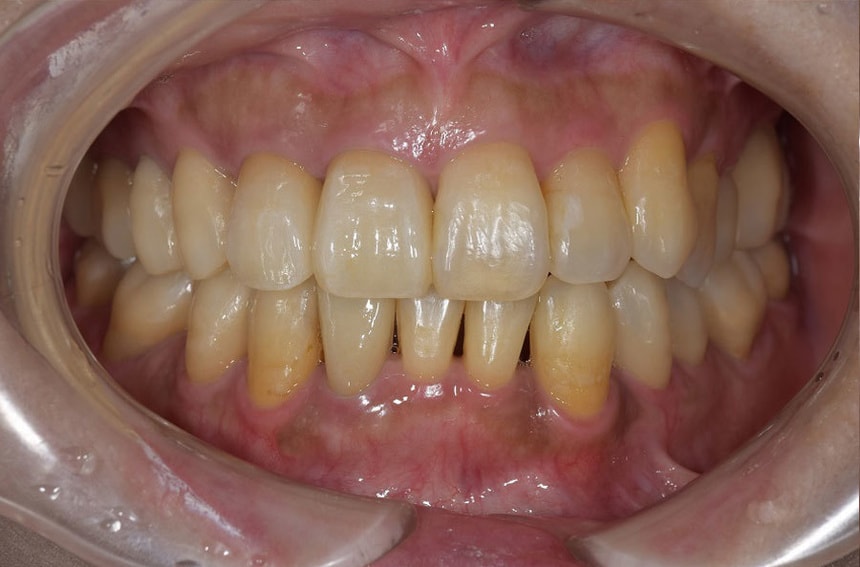

部分矯正を含めた全顎的な治療

前歯の治療前後

最小限の矯正治療や過去に治療した銀歯の隙間から虫歯になった歯や神経の再治療を行いました。もう少し修正が必要なのですが、部分矯正も含め長い治療になり、とりあえずはお疲れさまでした。

治療は、僕たちは当然ですが、患者さんにも頑張って頂いて初めてうまくいくものかなとも思います。定期的に通院していただいたり、治療が間延びしないことも治療がうまくいく要因の一つのように感じます。

治療が終了して終わりではなく、維持するためこれからメンテナンスが、始まると思っていただければ幸いです。現状が、できるだけ長期に維持できればと考えています。